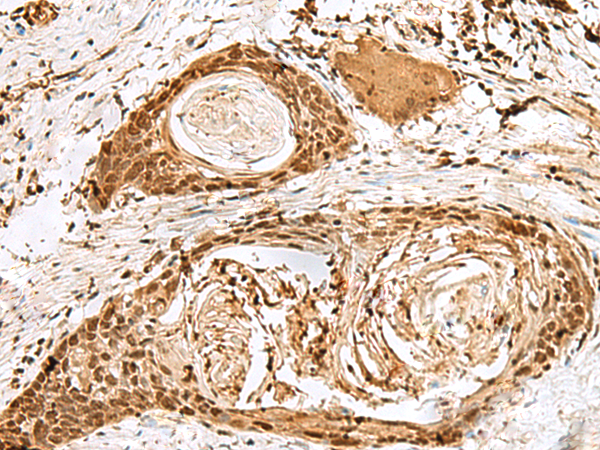

分类: 科研抗体货号: P09883别名: SS1; DRB1; HLA-DRB; HLA-DR1B应用: WB,IHC反应种属: Human